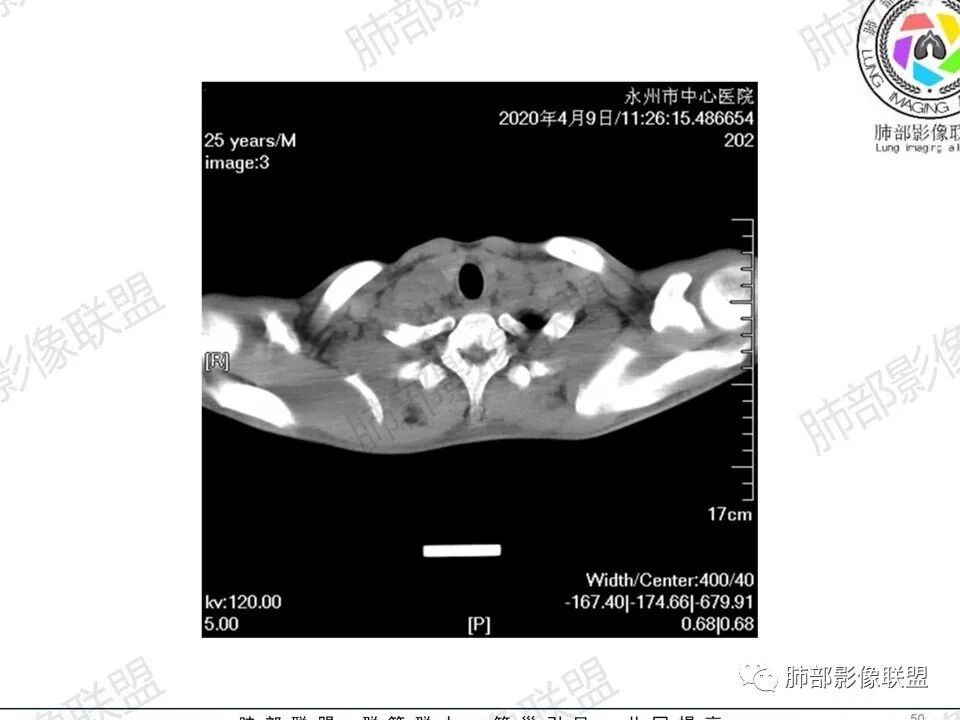

那个人:青年男性,慢性病程,咳嗽气促,伴盗汗胸痛。实验室,贫血,血沉快,C反应蛋白升高,低蛋白血症。影像,双肺散在斑片影,结节影,伴树芽,斑片影源支气管血管束分布,支气管走形自然,结节影有小空洞,有些周围有磨玻璃成分,小结节有些成串珠样改变,纵隔肺门淋巴结肿大,心腔低密度。考虑淋巴增值类疾病,结核?淋巴瘤?结节病?鉴别血管炎,实验室,影像不太支持

一切∮随缘:双肺多发大小不等结节,结节密度高,边缘清楚,部分结节内可见血管穿行,另右肺长条状实变影,内部可见支气管充气征,局部支气管壁增厚,双肺多发小树丫,双肺门及纵隔淋巴结肿大,部分融合,无增强,对淋巴结坏死无法判断,临床:年轻男性慢性病史急性加重,血象、CRP、ESR高,考虑一元论:结核(年龄加影像都符合),二元论:结节病或淋巴瘤+结核(建议CT增强及淋巴结穿刺),无原发肿瘤病史,癌性淋巴管炎代排。

3、影像表现:双肺散在斑片影及结节影,部分结节内可见血管穿行,斑片影沿支气管血管束分布,近胸膜侧病变收缩不明显。部分中央淋巴间质增厚,小叶间隔增厚。病灶内支气管穿行,部分支气管略扩张。局部小结节呈串珠样改变。纵隔、肺门区、锁骨上及腋窝淋淋巴结肿大,部分有融合。心腔低密度。脾大。

3.右肺较多微小结节,密度较为浅淡,部分沿血管束分布,未见沿小叶间隔及叶间裂分布结节影,未见典型的终末气道树芽。